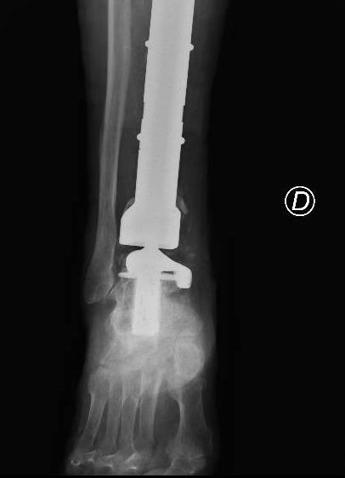

(Adnkronos) – Una protesi di caviglia costruita su misura salva la gamba bionica di Mario, paziente 80enne protagonista di un raro intervento eseguito al Policlinico Gemelli di Roma e definito "unico nel suo genere". Una travagliata storia a lieto fine cominciata una decina di anni fa quando Mario, ex coltivatore diretto, fu colpito da un cancro alle ossa. Ancora oggi, nonostante gli anni e gli acciacchi, Mario continua a occuparsi del suo orticello in una campagna in provincia di Viterbo. Ma sono tanti gli ostacoli che l'anziano ha dovuto superare e che sono iniziati 10 anni fa con un dolore sempre più forte e insistente alla gamba destra. Dopo una serie di esami, l'ortopedico consultato da Mario gli ha comunicato che quei fastidi erano causati da un tumore osseo raro (un adamantinoma) a carico della tibia. Alla diagnosi è seguita la resezione del tumore con impianto di una mega-protesi di tibia prossimale, cioè nell'area vicino al ginocchio. Dopo circa un anno dall'intervento, però, una grave infezione della protesi impiantata ha costretto Mario a subire una serie di complessi interventi chirurgici che si sono conclusi con l'impianto di una protesi totale di gamba e di caviglia in titanio, rivestita in argento per evitare nuove infezioni. Una gamba bionica. Ma ancora non era finita. A distanza di 6 anni, Mario torna dagli ortopedici del Gemelli per un dolore alla caviglia. Gli esami rilevano la rottura di una vite della protesi, a livello della caviglia. E' necessario sostituire il pezzo, ma l'unico modo per farlo – decretano gli specialisti – è facendo confezionare una protesi 'custom-made', disegnata e realizzata su misura. Gli ortopedici del Gemelli inviano perciò la Tac di Mario all'Implantcast, una ditta specializzata di Buxtehude, cittadina a sud ovest di Amburgo, in Germania. Basandosi sulla ricostruzione tridimensionale della caviglia bionica di Mario, i bioingegneri realizzano un calco della protesi custom-made con una stampante 3D, sul quale viene realizzata la protesi in titanio per l'impianto definitivo. Ed ecco l'intervento effettuato da Carlo Perisano, professore aggregato dell'Università Cattolica del Sacro Cuore e dirigente medico presso la Uoc di Ortopedia e Traumatologia della Fondazione Policlinico Gemelli, diretta da Giulio Maccauro. L'operazione dà i suoi frutti: "A distanza di appena qualche giorno dall'intervento, Mario sta di nuovo in piedi sulla sua gamba bionica arricchita di quest'ultimo gioiello tecnologico", riferiscono dall'Irccs capitolino. (segue) —salutewebinfo@adnkronos.com (Web Info)